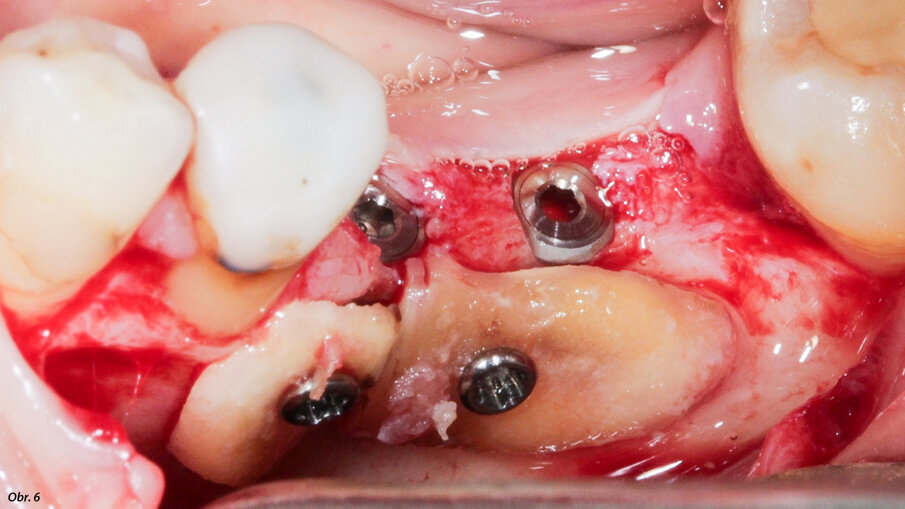

Kořeny byly vytvarovány tak, aby pasovaly do místa defektu a jsou

v místě transplantace zajištěny osteosyntetickými šroubky.

Měli jsme tři alternativní možnosti postupu: štěp kostního bloku z ramene dolní čelisti, segmentální osteotomii nebo radikulární štěp s vědomím, že zub 46 nebude vzhledem k jeho poškození možné zachránit. Zvolili jsme třetí možnost, protože umožňovala současné zavedení implantátu a rekonstrukci kosti. Byl odklopen rozsáhlý lalok, aby mohl být posouzen defekt kosti a uzavřen augmentovaný hřeben. Jako obvykle byly zavedeny dva implantáty, navzdory malé tloušťce reziduální kosti ve vestibulární oblasti plánovaných pozic pro implantáty (obr. 5). Kořeny zubu 46 byly atraumaticky extrahovány (separace kořenů byla provedena pomocí piezochirurgie) a připraveny podle výše uvedeného popisu. Kořeny byly vytvarovány tak, aby odpovídaly defektu a v oblasti transplantace byly zajištěny pomocí osteosyntetických šroubků (obr. 6). Lalok byl mobilizován a natažen tak, aby došlo k uzavření oblasti „end to end“ bez tahu, a k sešití bylo použito rychle vstřebatelné splétané vlákno č. 4/0 (obr. 7). Čtyři měsíce po augmentaci kosti a zavedení implantátu byly na implantáty umístěny vhojovací válečky a odstraněny osteosyntetické šroubky (obr. 8, 9). Během zákroku byl čas provést vizuální kontrolu toho, zda byla ankylóza radikulárních štěpů úspěšná a zda jsou štěpy zdravé. Nakonec bylo provedeno vyšetření pomocí CBCT. Náhradu nasadil náš kolega o několik týdnů později, jakmile byly zhojeny měkké tkáně.